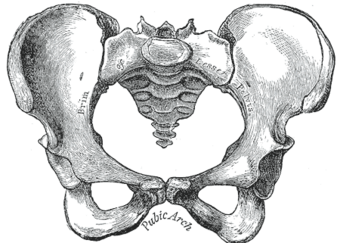

Pelvic bone

قالب:Pelvis image The pelvic skeleton is formed posteriorly (in the area of the back), by the sacrum and the coccyx and laterally and anteriorly (forward and to the sides), by a pair of hip bones. Each hip bone consists of three sections: ilium, ischium, and pubis. During childhood, these sections are separate bones, joined by the triradiate cartilage. During puberty, they fuse together to form a single bone.

A distinction is made between the lesser or true pelvis inferior to the terminal line, and the greater or false pelvis above it. The pelvic inlet or superior pelvic aperture, which leads into the lesser pelvis, is bordered by the promontory, the arcuate line of ilium, the iliopubic eminence, the pecten of the pubis, and the upper part of the pubic symphysis. The pelvic outlet or inferior pelvic aperture is the region between the subpubic angle or pubic arch, the ischial tuberosities and the coccyx. [2]